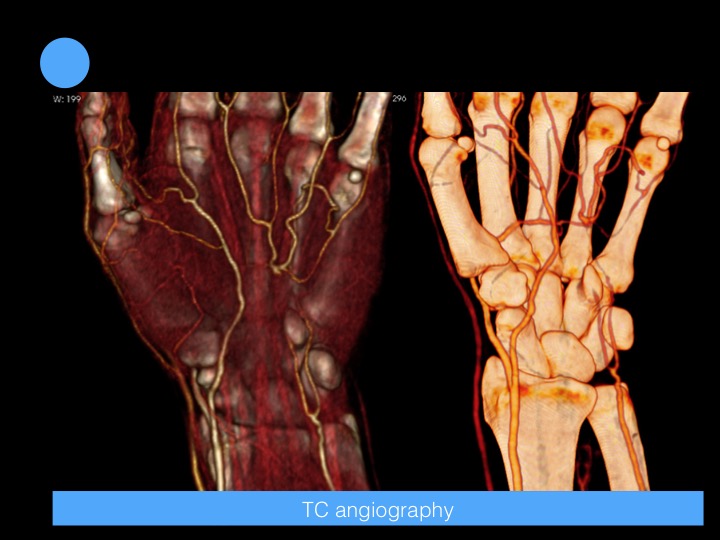

45-year-old man with unspecific pain and numbness in the hypothenar eminence

Hypothenar hammer syndrome is caused by blunt repetitive injury to the ulnar artery and superficial palmar arch from impact against the hamulus. Palmar arches and digital arteries also may be occluded.

Intimal hyperplasia is almost invariably present. Arterial wall damage may lead to aneurysm formation with or without vessel thrombosis and to microemboli formation and compression of the sensory branch of the ulnar nerve.

The diagnosis can be confirmed easily with Doppler ultrasound. However, CT angiography, or MR angiography is for precise vascular mapping. Reference article.

Hypothenar Hammer Syndrome